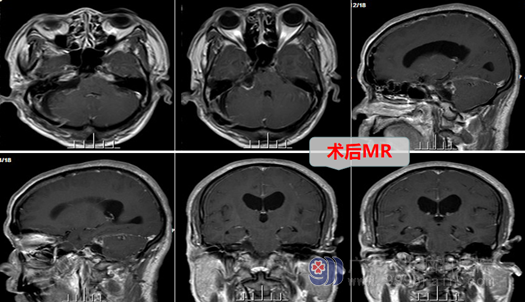

经完善术前准备排除手术禁忌症后,欧阳教授带领外十科医生团队制定了详细的手术计划,决定在全麻下为梁大叔实施:右侧桥小脑角区占位(肿瘤)切除术。手术中在显微镜放大下进行,术中可见肿瘤位于右侧桥小脑角,右侧耳蜗神经、面神经位于肿瘤前下方,三叉神经位于肿瘤上方,经仔细分离,面神经、三叉神经、舌咽神经等虽受肿瘤压迫明显,但均被保留完整,肿瘤全切。术后梁大叔返回监护室接受照护,生命体征平稳,对答正确,能够遵嘱活动。

手术后,梁大叔面部三叉神经痛一次都没有发作过,能够顺利切除肿瘤,尤其是面部不痛了,一家人都很满意手术效果,目前梁大叔正在接受术后康复治疗。